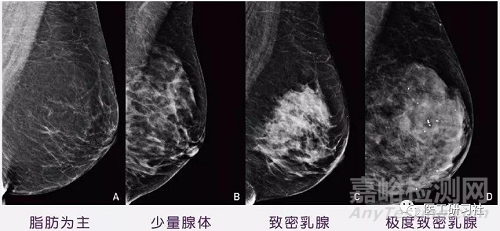

和胸大胸小沒關(guān)系,乳腺密度才是關(guān)鍵。因?yàn)椋?)致密乳腺得乳腺癌發(fā)病率更高一些,罹患風(fēng)險(xiǎn)提高4-6倍;2)致密性乳腺更容易漏診,比如乳腺X射線診斷乳腺癌的敏感性為 85%,若密度較高,敏感性降至 47.8%~64.4%。

在醫(yī)學(xué)上,脂肪少、腺體多的乳房,被稱為“致密性”。因脂肪少導(dǎo)致胸小的女性,是致密性乳腺的幾率更大,可以說“平胸”比“大胸”相對更容易患乳腺癌。根據(jù)數(shù)據(jù),亞洲人在年輕階段致密乳腺占38%,歐美僅20%。

另外,需要說明得是,乳房是否致密與乳房硬度無關(guān),并不能通過自我乳房檢查確認(rèn),只有影像檢查才可以。比如,在乳腺X射線檢查中,致密乳腺組織看上去是白色或淺灰色,而乳腺癌也均呈白色,因此有時(shí)會掩蓋病灶。

乳腺X射線下不同類型乳腺(來自互聯(lián)網(wǎng))